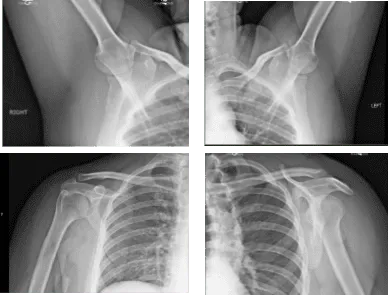

En cirugías anteriores, ninguna. El paciente presentó resultados de radiografías que mostraron radiografías poco destacables del hombro bilateral.

Hombros bilaterales por rayos X